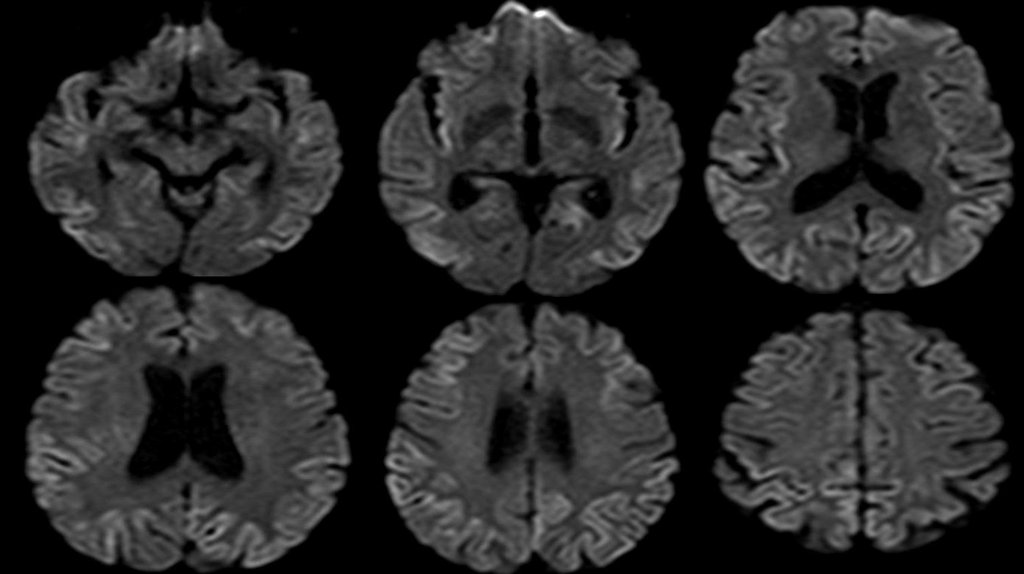

Выявляются множественные асимметричные зоны повышения МР-сигнала на DWI и FLAIR ИП с

вовлечением коры теменных (преимущественно), лобных, затылочных и височных долей (D>S).

В субкортикальных отделах белого вещества лобных и теменных долей выявляются

множественные очаги гиперинтенсивного МР-сигнала на Т2 ВИ и FLAIR ИП размером до 5мм

Заключение:

МР-признаки поражения коры больших полушарий головного мозга. Учитывая анамнез, в

первую очередь необходимо дифференцировать с болезнью Крейтцфельдта-Якоба; в

диф.ряду метаболические (печеночная энцефалопатия), гипоксические изменения маловероятно.

Множественные сосудистые очаги в белом веществе полушарий головного мозга. Расширение

наружных и внутренних ликворных пространств.